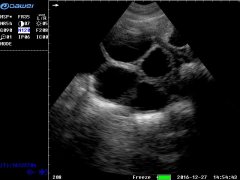

大為便攜式彩色獸用B超儀照出圖效果

徐州市大為電子設備有限公司是集自主研發、生產、銷售醫用超聲、獸用B超產品于一體的專業廠家。大為獸用B超經過快10年的發展,產品更新換代,質量突...